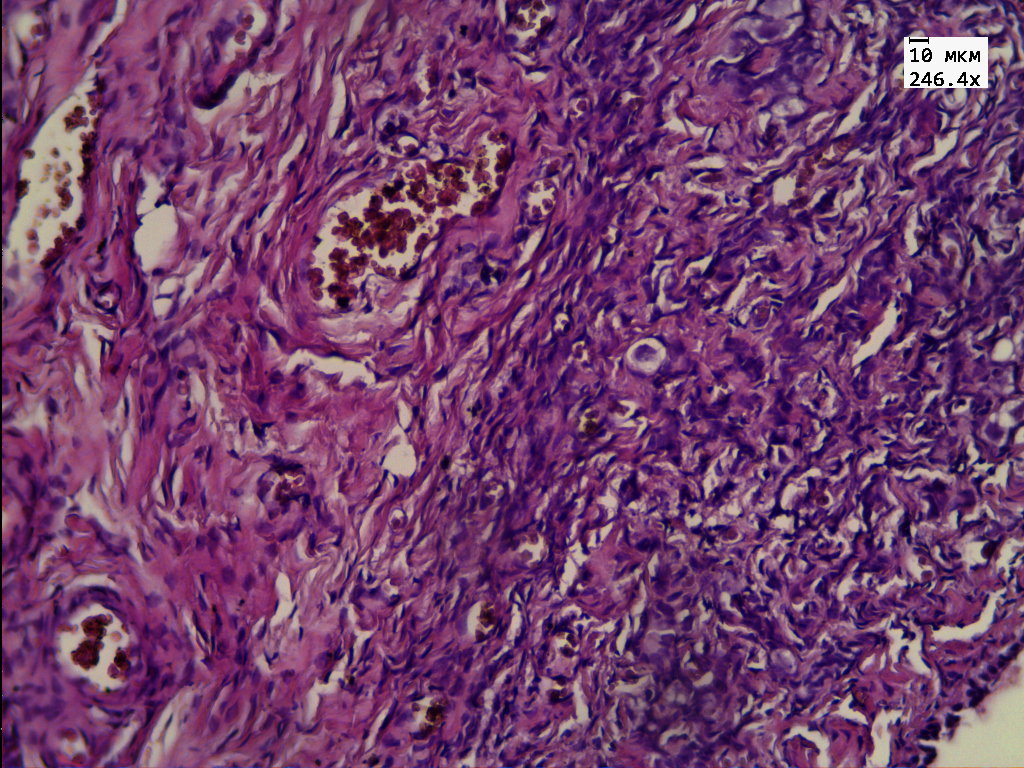

Гистологическое исследование интраоперационного материала гонад показало наличие ткани яичка и яичника, разделенных фиброзной прослойкой. Ткань яичника фиброзирована, деление на корковый и мозговой слой нечеткое. В корковом слое определяются примордиальные фолликулы с выраженными дистрофическими изменениями (рис. 1, на цв. вклейке). Ткань яичка разбита на дольки фиброзными прослойками, единичные микрокальцинаты. В эпителии канальцев резко выраженные дистрофические и пролиферативные изменения: увеличение размеров клеток, ядер, гиперхромия ядер. Клетки сперматогенного эпителия располагаются хаотично и находятся в разной степени зрелости. Обращают на себя внимание крупные клетки с четко определяемым ядром и наличием в нем ядрышек — половые клетки (рис. 2, на цв. вклейке). Такое строение сперматогенного эпителия соответствует организации, характерной для антенатального периода [4].

Рис. 1. Микроскопическая картина ткани яичника: диф- ференцировка на корковый и мозговой слой, в корковом слое примордиальные фолликулы с дистрофическими изменениями. Окраска гематоксилином и эозином, ув. 250.

Результаты гистологического исследования гонад нашего пациента показали наличие незрелой тестикулярной ткани с выраженными пролиферативными изменениями, микрокальцинатами. В ткани яичника отсутствовало четкое деление на корковое и мозговое вещество. Примордиальные фолликулы, определяемые в овариальной части гонады, имели выраженные дистрофические изменения. На основании этих данных было принято решение о проведении гонадэктомии.